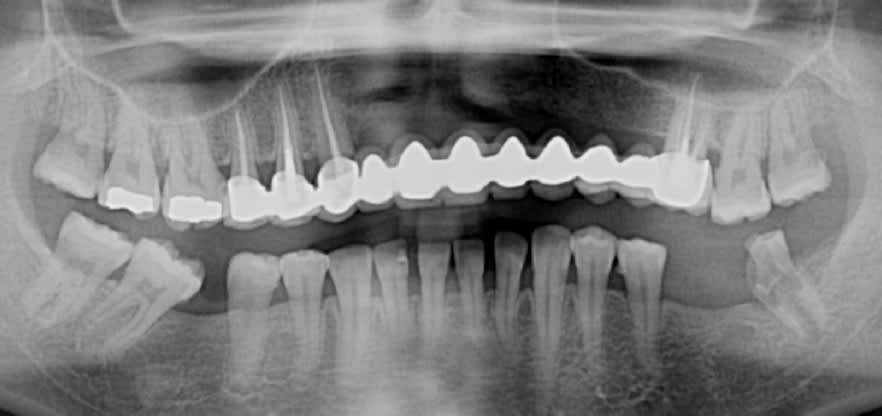

Ici une 37, complètement asymptomatique après un "soin" remontant à 5 ans...

Image extraite d'une pano.